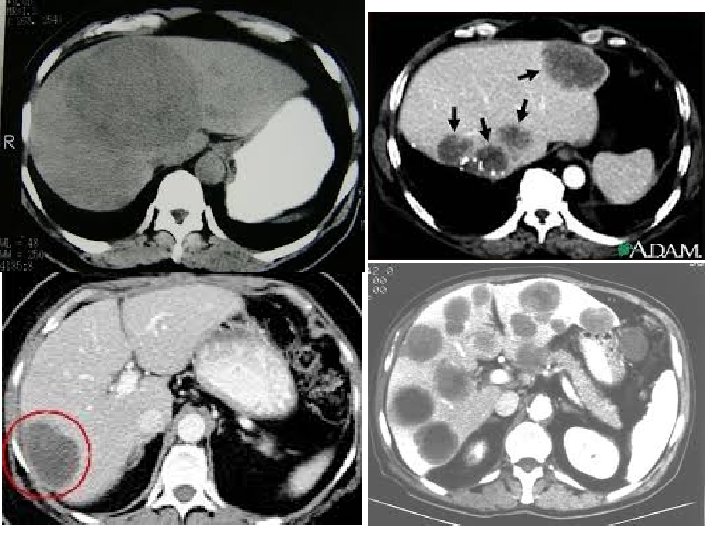

Diagnosis • CT

CT • Computed tomography - medical imaging method employing tomography (imaging by sections or sectioning) • Large series of two-dimensional X-ray images taken around a single axis of rotation, computer integration • Iodine dye through vein for better visualisation (allergy)

Imaging Studies: • • Plain radiography Ultrasound examination CT scaning MRI